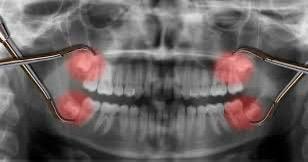

هناك تصور أن ضرس العقل يظهر فى سن متاخرة ليضم جميع الأسنان ويغلق المسافات المفتوحة بين الأضراس فتمنع تراكم الفضلات وعدد ضرس العقل أربعة إثنان بالفك العلوى واثنان بالفك السفلى.

ونظراً لأنها اخر الأسنان التى تظهر بالفم ففى اغلب الاحيان لاتجد لها مكاناً بالفم وبالتالى

إما ان تظل مدفونة فى عظام الفك كلية ، أو تحاول البزوغ جزئياَ، أى يظهر جزء منها بالفم والباقى مدفوناَ بعظام الفك .